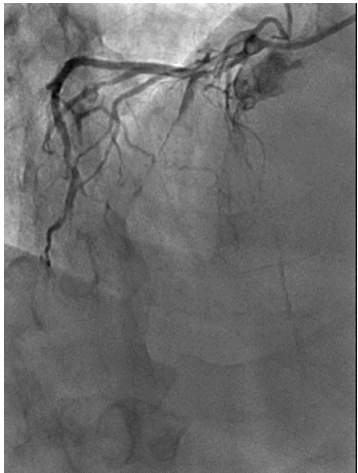

The patient then underwent elective coronary angiography which showed a Normal Left Main,  100% occluded Left Anterior Descending Artery, filling from right sided collaterals, a proximal 80% in the left circumflex with a 99% occluded OM1. The RCA had a proximal 80% lesion with a diffusely diseased acute marginal branch.

Figure 4 LAO cranial view showi ng 100% occluded LAD